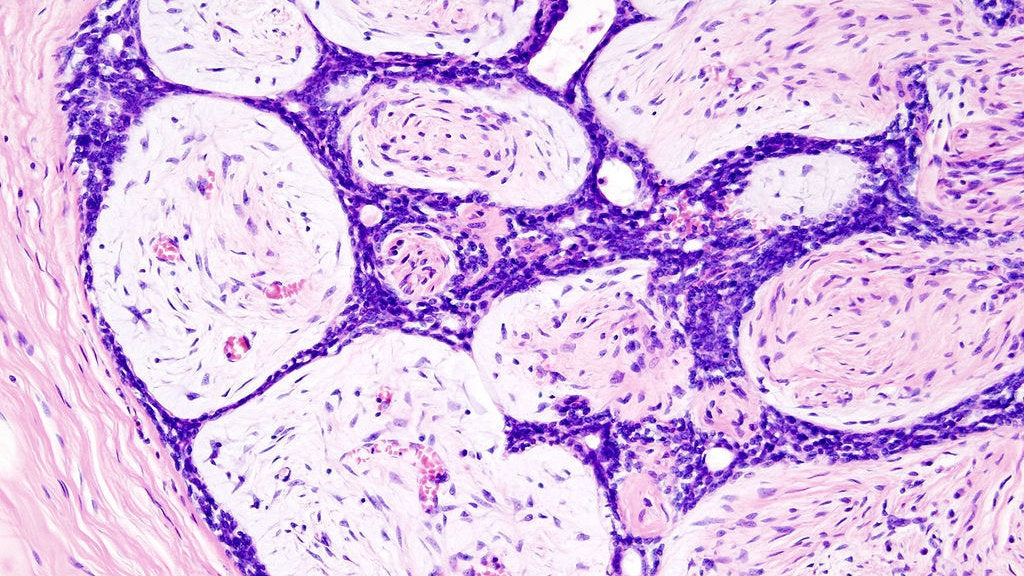

Fibroadenomas are benign breast tumours characterized by an admixture of stromal and epithelial tissue. Breasts are made of lobules (milk producing glands) and ducts (tubes that carry the milk to the nipple). These are surrounded by glandular, fibrous and fatty tissues. Fibroadenomas develop from the lobules. The glandular tissue and ducts grow over the lobule to form a solid lump.